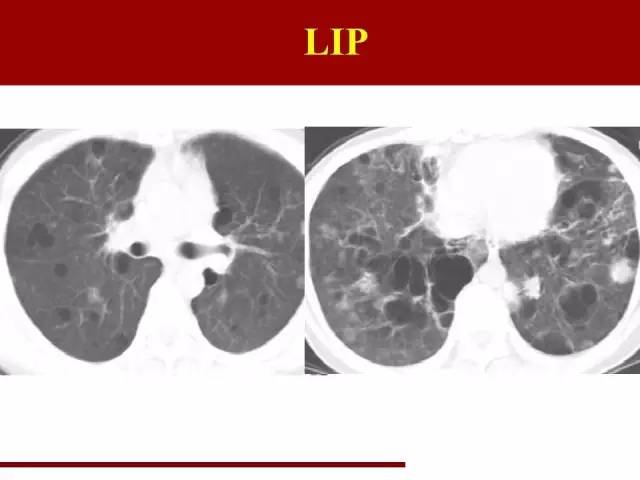

LIP同样是一类疾病的不同阶段,前身是滤泡性细支气管炎

但是滤泡性细支气管炎同样时间很短,目前还没有诊断过。

LIP的特点很典型,在幻灯片里已经说过了

袁怀平:

典型的图片,大家一看就能明白